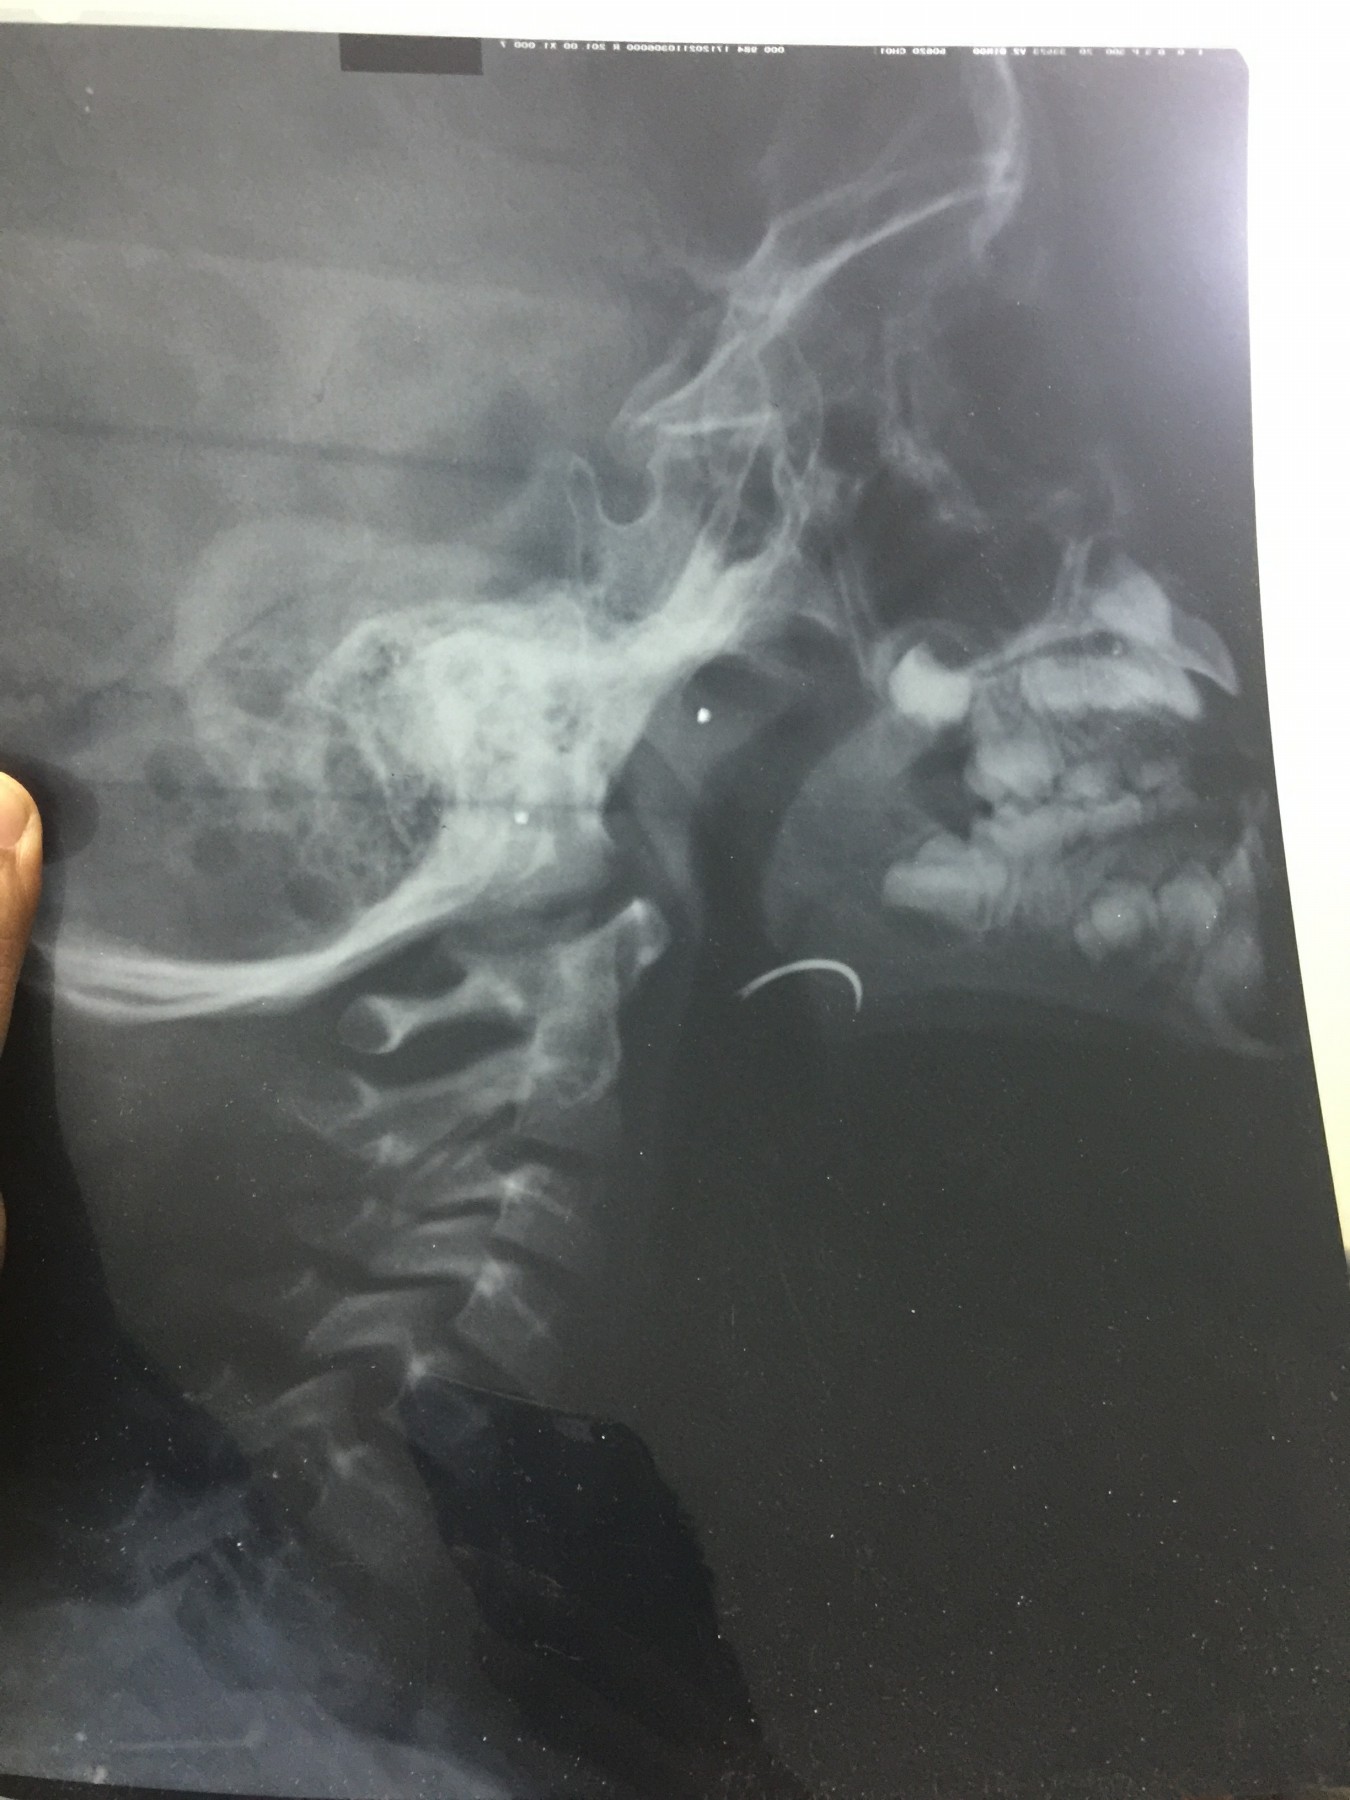

شهد مسلسل الإهمال الطبى حلقة جديدة بمستشفى جامعة طنطا، حيث نسى أحد الأطباء إبرة الخياطة الخاصة بالجروح داخل حنجرة أحد الأطفال خلال إجراء علمية جراحية لإزالة اللوزتين.

وأكد والد الطفل، أن الطبيب اكتشف أنه نسي الإبرة داخل زور نجله، وقام بتخدير نجله مرة ثانية لإخراج الإبرة ولكن دون فائدة، مؤكدا أن الطبيب أكد انه لن يستطيع استخراج الإبرة من الطفل.

وأكد، أنه توجه للدكتور أمجد عبد الرؤوف عميد كلية الطب، والدكتور هشام توفيق المشرف العام على المستشفيات الجامعية للتدخل لإنقاذ نجله، مشيرا إلى أنه تقدم بشكوى ضد الطبيب الذي أجرى العملية “أ.س” لرئيس قسم الأنف والأذن بالمستشفى، وعميد كلية الطب والمشرف العام على المستشفيات الجامعية، مؤكدا أن رئيس قسم الأنف والأذن والحنجرة، استدعى أطباء من خارج المستشفى لإنقاذ نجله، وأكدوا أن فى ذلك خطورة على حياته.